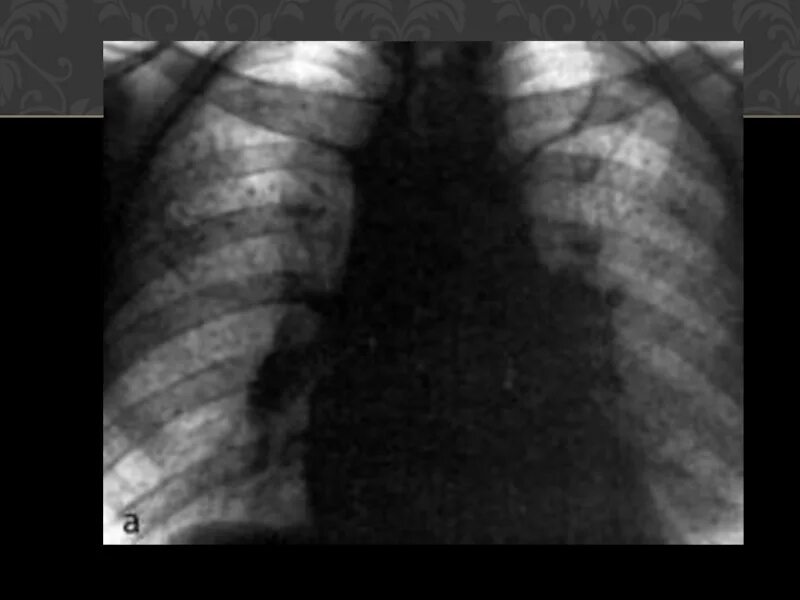

Бронхоаденит это